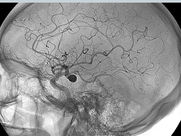

Anevrizma: Arter çapının normalin %50’sinden fazla genişlemesi.

En sık: Abdominal Aort Anevrizması (AAA)